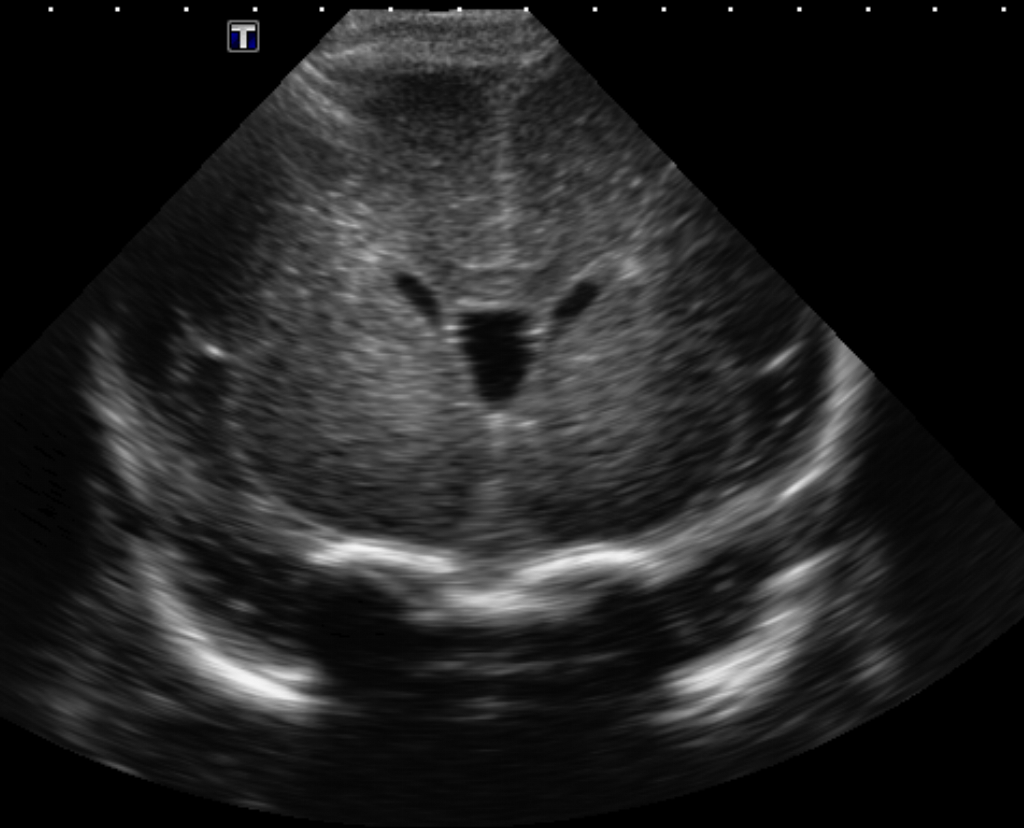

Brain

The brain is immature. [Yes/No]

There is under-sulcation and open sylvian fissures. [Yes/No]

There is/are multiple hypoechoic areas in the periventricular white matter. [Yes/No]

There is/are multiple hyperechoic areas in the periventricular white matter. [Yes/No]

There is diffuse cerebral edema with diffusely increased echogenicity of the brain parenchyma and loss of grey white matter differentiation. [Yes/No]

The thalami/basal ganglia are hypoechoic. [Yes/No]

There is periventricular calcification. [Yes/No]

There is intra-parenchymal calcification. [Yes/No]

CSF spaces/ventricular system

There is prominence of the ventricular system. [Yes/No]

There is a cavum septum pellucidum. [Yes/No]

There is a midline shift towards right/left. [Yes/No]

The third ventricle is dilated. [Yes/No]